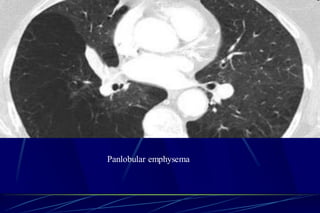

Panlobular Emphysema

Affects the whole secondary lobule

Lower lobe predominance

In alpha-1-antitrypsin deficiency, but

also seen in smokers with advanced

emphysema

Affects the entire secondary pulmonary lobule

and is more pronounced in the lower zones

Complete destruction of the entire pulmonary

lobule.

Results in an overall decrease in lung

attenuation and a reduction in size of

pulmonary vessels